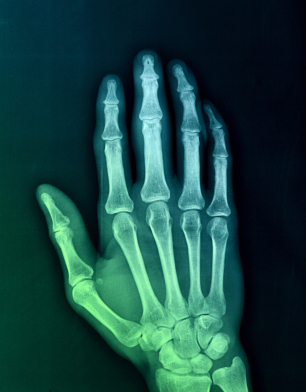

4) Is there a correlation of x-ray images of arthritis and the severity of the symptoms?

5) What is basilar joint arthritis?